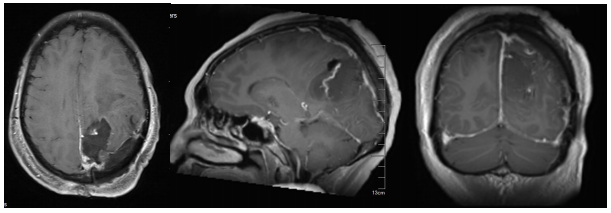

秦婆婆近期常常出现头晕、头痛的症状,还伴有双下肢乏力,导致走路不稳,本以为是“上了年纪”,并未引起重视,但症状却持续加强,逐渐影响正常生活。近日,家人陪同秦婆婆到泰康同济(武汉)医院求诊于泰康医疗神经医学中心首席专家陈劲草教授。通过头颅MRI检查发现其左侧顶部大脑镰旁存在一肿瘤性病变,初步诊断为脑膜瘤。经进一步核磁共振增强扫描确认,肿瘤大小约为53毫米×46毫米×49毫米,属于巨大脑膜瘤。

图片2.png术前影像检查

由于肿瘤位置紧邻大脑中负责静脉血液回流和脑脊液循环的重要“管道”及神经系统,手术风险极高,术中易引发大出血,术后还可能出现视力障碍、言语功能受损、偏瘫、癫痫等严重并发症。面对这一挑战,陈劲草组织全科进行病例讨论,制定周密手术方案,决定在显微镜下为患者实施“左侧大脑镰旁顶叶巨大肿瘤切除术”。